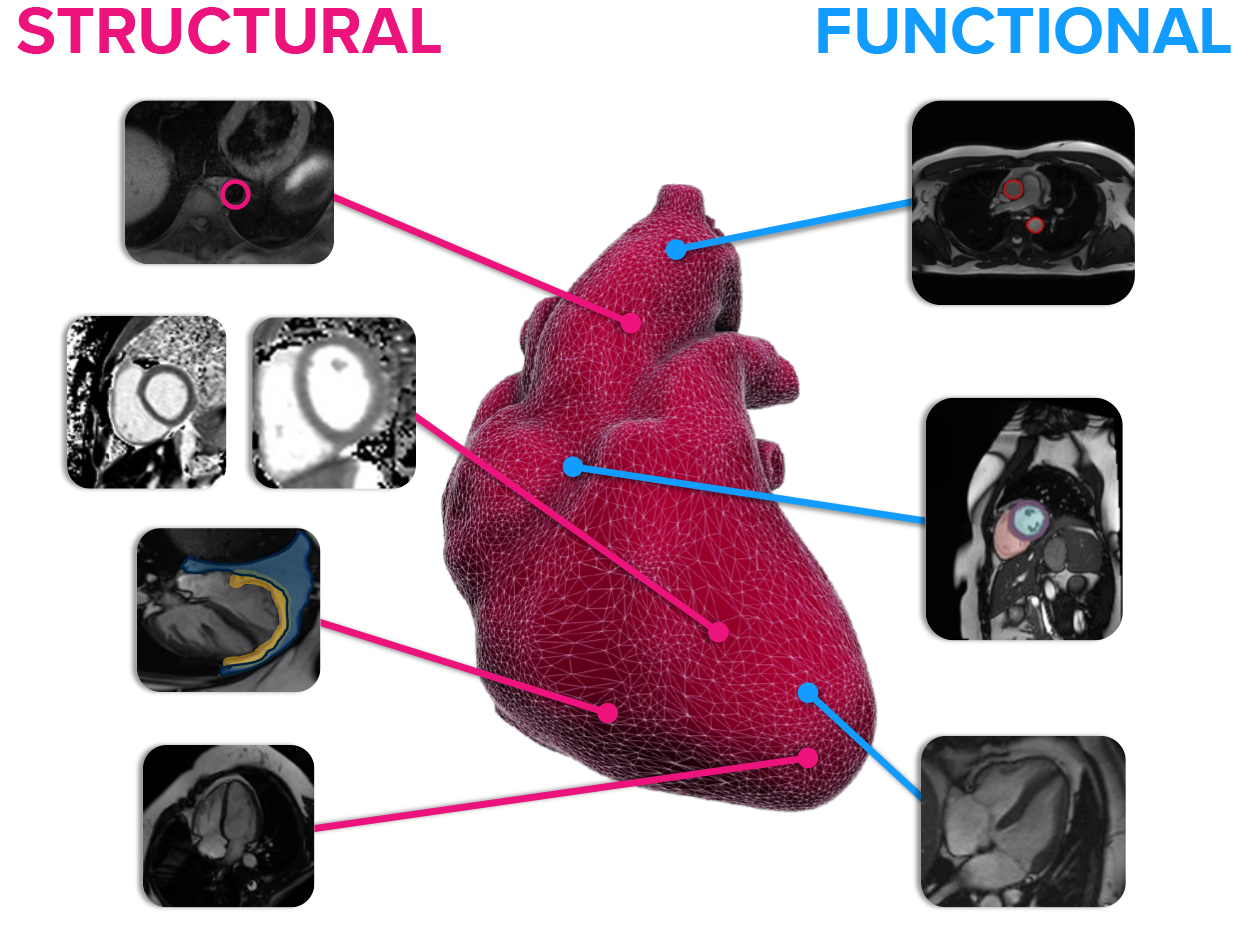

Cardiac imaging

Using our cardiac imaging services, comprehensive assessments of cardiac structure and function can be carried out in a sub 30 minute non-contrast scan – maximising patient comfort and scanner capacity.